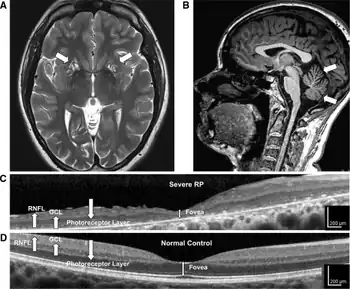

Neuropathy, ataxia, and retinitis pigmentosa, also known as NARP syndrome, is a rare disease with mitochondrial inheritance that causes a variety of signs and symptoms chiefly affecting the nervous system[1] Beginning in childhood or early adulthood, most people with NARP experience numbness, tingling, or pain in the arms and legs (sensory neuropathy); muscle weakness; and problems with balance and coordination (ataxia). Many affected individuals also have vision loss caused by changes in the light-sensitive tissue that lines the back of the eye (the retina).[2][3] In some cases, the vision loss results from a condition called retinitis pigmentosa. This eye disease causes the light-sensing cells of the retina gradually to deteriorate.